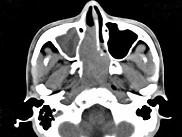

问题 男,20岁,头痛、鼻塞、鼻出血,CT如图所示,最可能诊断为()

选项 A.鼻咽癌 B.巨大的鼻息肉 C.鼻咽纤维血管瘤 D.鼻咽神经纤维瘤 E.鼻咽腺样体增生

答案 C